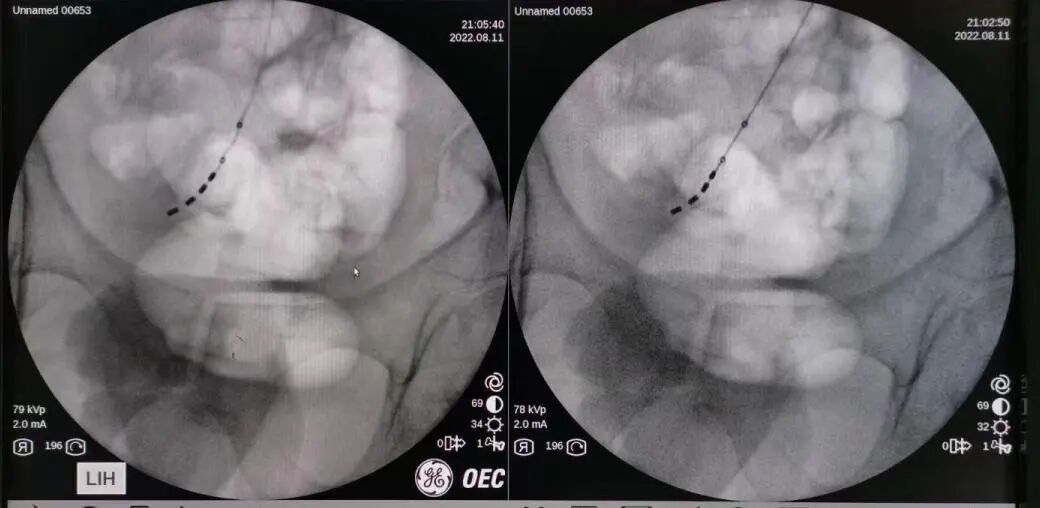

2022年8月11日,在李碧锦主任的殷切指导下,李超文副主任携团队李军副主任医师、杨家冠医师作为手术助手为彭先生进行了 I 期电极植入手术,术中电极植入位置精准,各位点运动应答、感觉应答明显,测试效果满意。术后开机当天彭先生自觉效果良好,目前处于测试体验阶段,期待彭先生从该疗法中获益更多。

电极植入位置精准